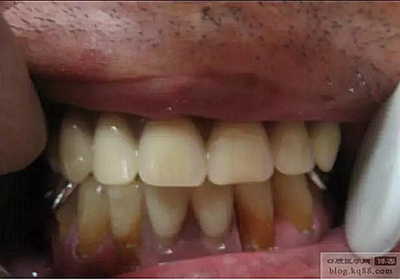

試排牙,外形和笑線都達(dá)到了預(yù)期效果。

調(diào)頜后戴入口內(nèi)的照片,穩(wěn)固程度,美觀程度,豐滿度患者均很滿意。